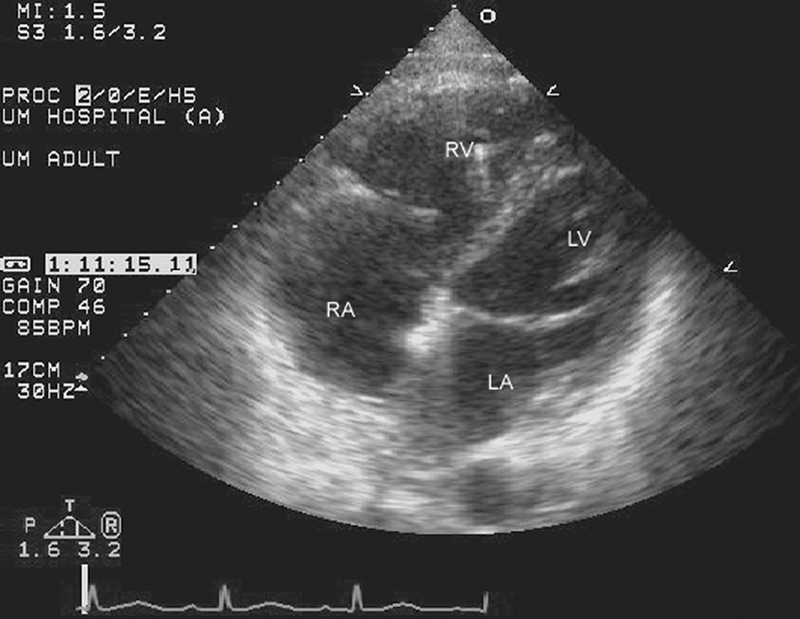

فحوصات تشخيصية لبعض امراض القلب والشرايين التاجية